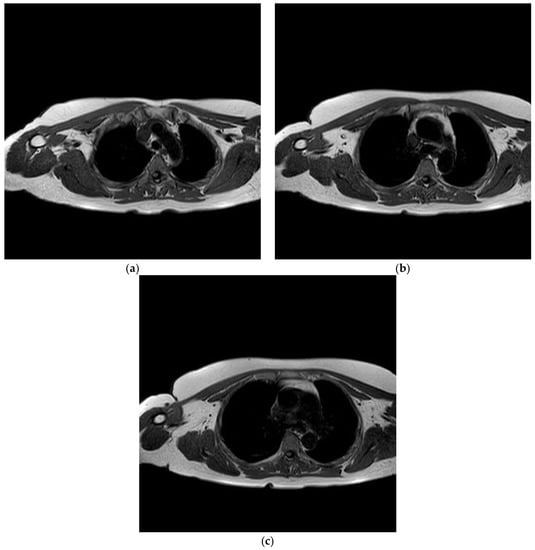

Laboratory investigations revealed raised inflammatory markers, with a white cell count (WCC) of 9.62 × 109/L, neutrophils of 8.73 × 109/L, and a C-reactive protein (CRP) of 52 mg/L. Radiographs of the right shoulder were obtained (Figure 1a,b), and were unremarkable.

Figure 1. (a,b) Radiographs of the right shoulder.